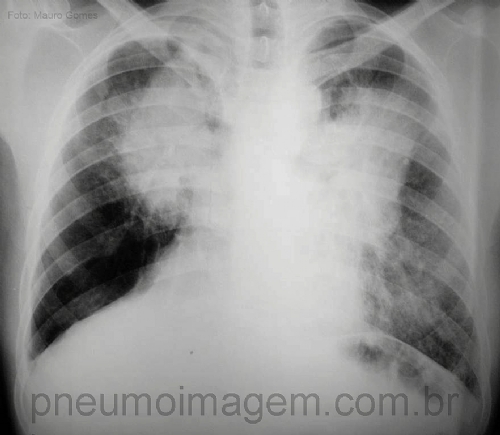

CASO CLÍNICO #15Homem de 55 anos, tabagista, trabalhava no Ceará com a construção de poços. Compareceu à consulta com esta radiografia para avaliação de massa pulmonar por suspeita de neoplasia. Você concorda com essa suspeita de neoplasia? Qual a sua hipótese diagnóstica? Deixe seus comentários abaixo.

Man, 55 years-old, smoker, worked with the construction of wells, he came up with this radiography for evaluation of pulmonary mass on suspicion of neoplasia. Do you agree with this diagnosis? What is your hypothesis? Let your comments below.